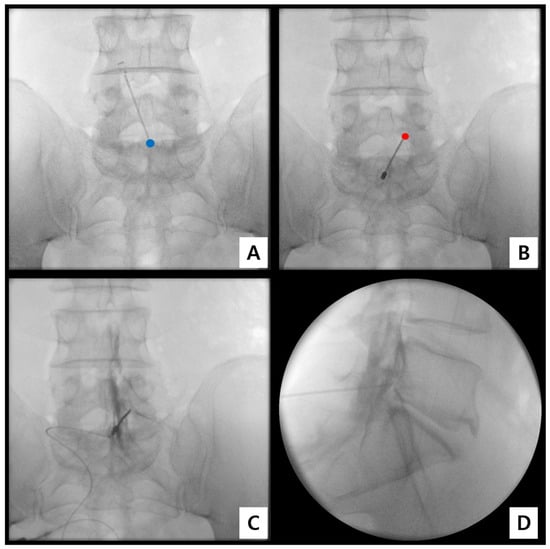

2.3. Procedural Technique for Catheter-Free LIVEI at L5–S1

- Step 1. Fluoroscopic target identification (AP)

- Step 2. Midline entry and bone docking

- Step 3. Interlaminar epidural access confirmation

- Step 4. Controlled ventral advancement (“saline cushion” technique)

- Step 5. Fluoroscopic confirmation of ventral epidural positioning

- Step 6. Final injectate delivery

3.2. Fluoroscopic Findings

| Grade 3 | Anterior (ventral) spread with foraminal extension involving ≥ 2 levels | 8 (66.7%) |

| Grade 2 | Anterior (ventral) spread with limited foraminal involvement | 4 (33.3%) |

| Grade 1 | Posterior-only or absence of anterior (ventral) spread | 0 (0%) |

| Total | Ventral epidural spread confirmed | 12 (100%) |